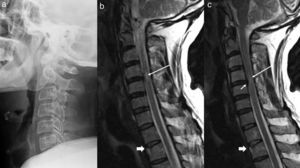

On occasion, the MRI of the affected region may be normal, but there may be remote lesions in the rachis, which act as markers of the mechanism of injury (Fig. 3). If these regions are not included in the MRI, this may be normal. Thus, it is advisable for the study to include an extensive area of the rachis believed to be affected, or at times more than one region, as there is also the problem of non-contiguous lesions.28

Lateral radiograph of the cervical column (a) and MRI of the cervical column with weighted sagittal sequences in T1 (b) and T2 (c). In the lateral radiograph, only a straightening of the lordosis can be observed. The MRI images show an irregularity and alteration in the signal for the upper D2 disc, consistent with a compression fracture (thick arrows in b and c). A small central protrusion can be observed at C4–C5 level (arrow in c), which associates a slight reduction in the canal and an area of spinal cord oedema (long arrows in b and c).

On occasion, information on the diagnosis is provided by the joint analysis of a number of tests. For example, CT may be useful for providing information on the previous state, and MRI on the latter and the acute repercussions thereof (Fig. 4).

Sagittal reconstruction of cervical CT (a) and STIR sequence of MRI (b) on sagittal planes. The patient exhibited an initial tetraparesis from which he recovered within a few hours. The image shows a posterior osteophyte C6–C7 (a), as well as an image of hypertrophy of the posterior longitudinal ligament at the same level. This previous state could probably have caused a spinal cord shock.